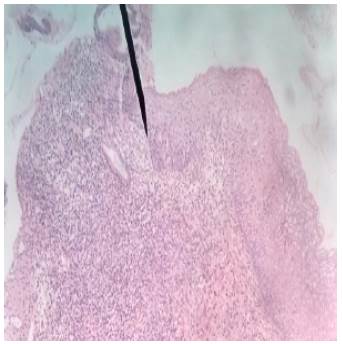

Melanoma lentiginoso acral con Breslow de 2.33mm con epidermis atrófica, proliferación de melanocitos en capa basal y presencia de atipia nuclear y mitosis. Tinción: Hematoxilina-Eosina. Vista: 40x.

Figura 2: Melanoma lentiginoso acral con Breslow de 2.33mm con epidermis atrófica, proliferación de melanocitos en capa basal y presencia de atipia nuclear y mitosis. Tinción: Hematoxilina-Eosina. Vista: 40x.

Fuente: Documento obtenido durante la realización del estudio.